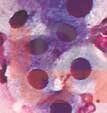

Цитологическая диагностика

Данная книга отражает современный уровень отечественной клинической цитологии, а также указывает на проблемы, которые необходимо решить для эффективной работы в будущем.

В  книге в логической последовательности представлены современные технологии традиционной и жидкостной цитологии, алгоритм выполнения цитологических исследований, освещены существенные преимущества цитологического метода перед другими методами морфологического исследования.

Для клинических цитологов, врачей различных специальностей, научных сотрудников, занимающихся вопросами клинической цитологии вообще и цитологической диагностики новообразований в частности.